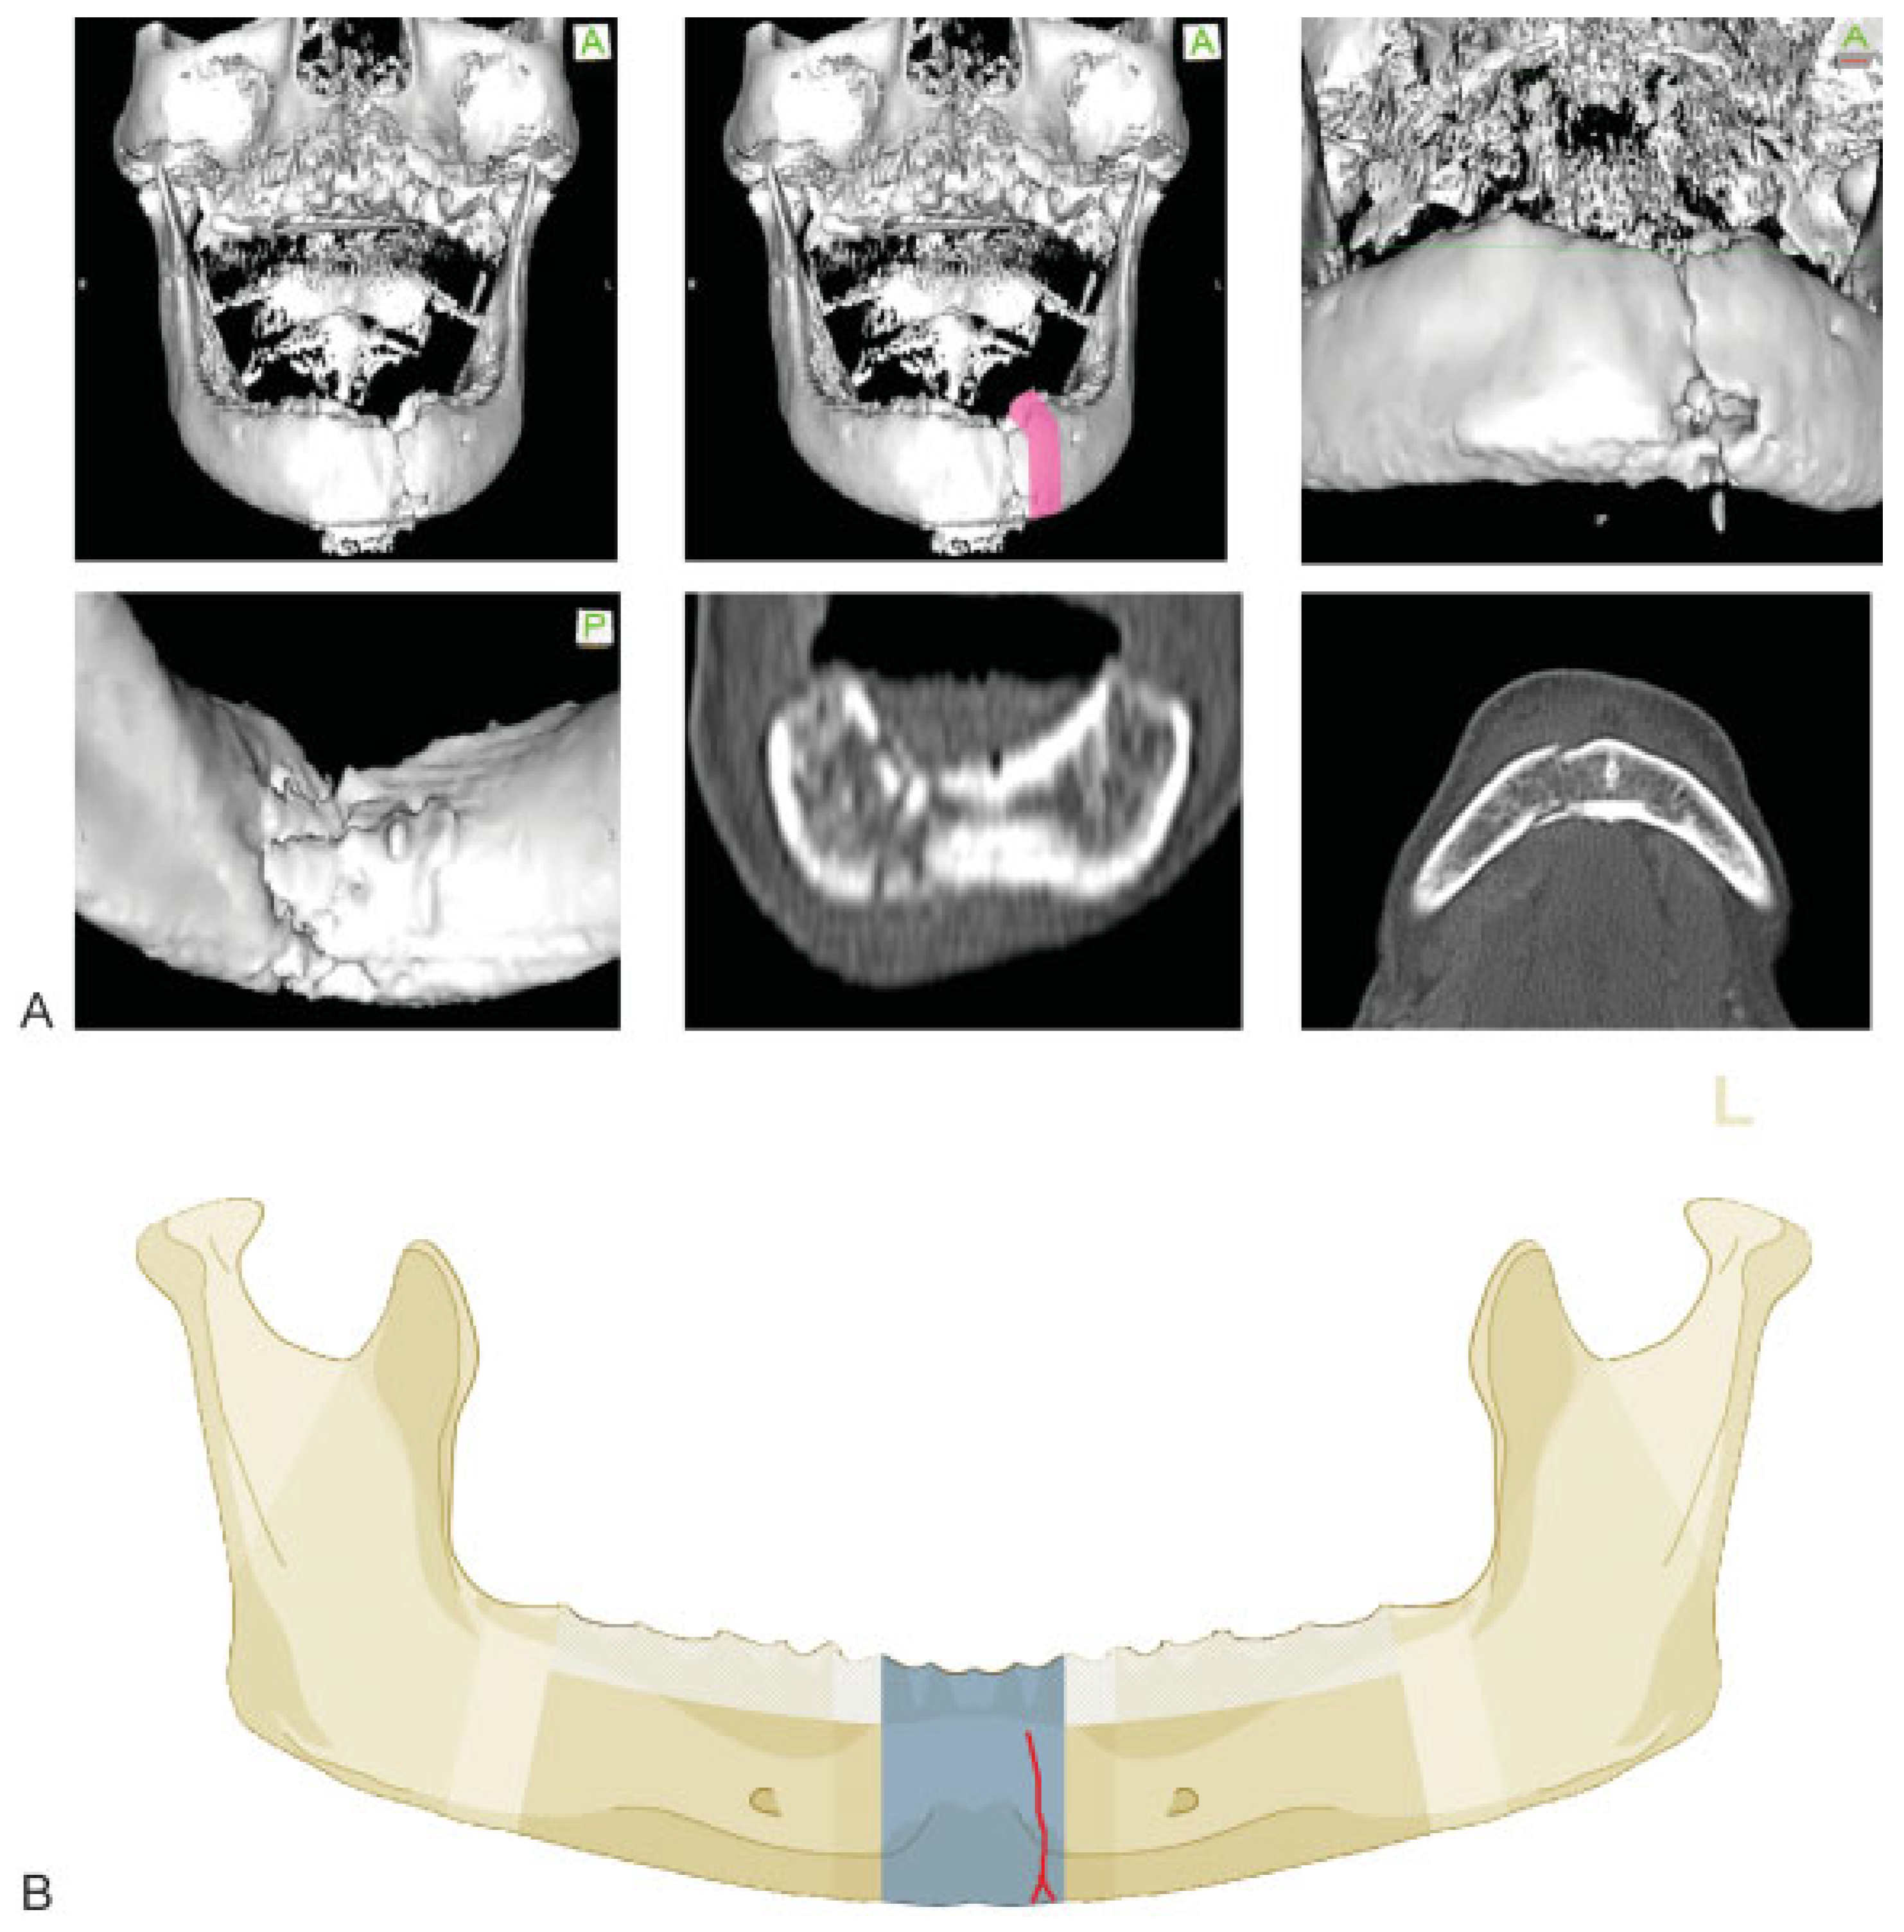

:Anatomical and Diagnostic Imaging Considerations

Symphysis/Parasymphysis Region

Case Examples